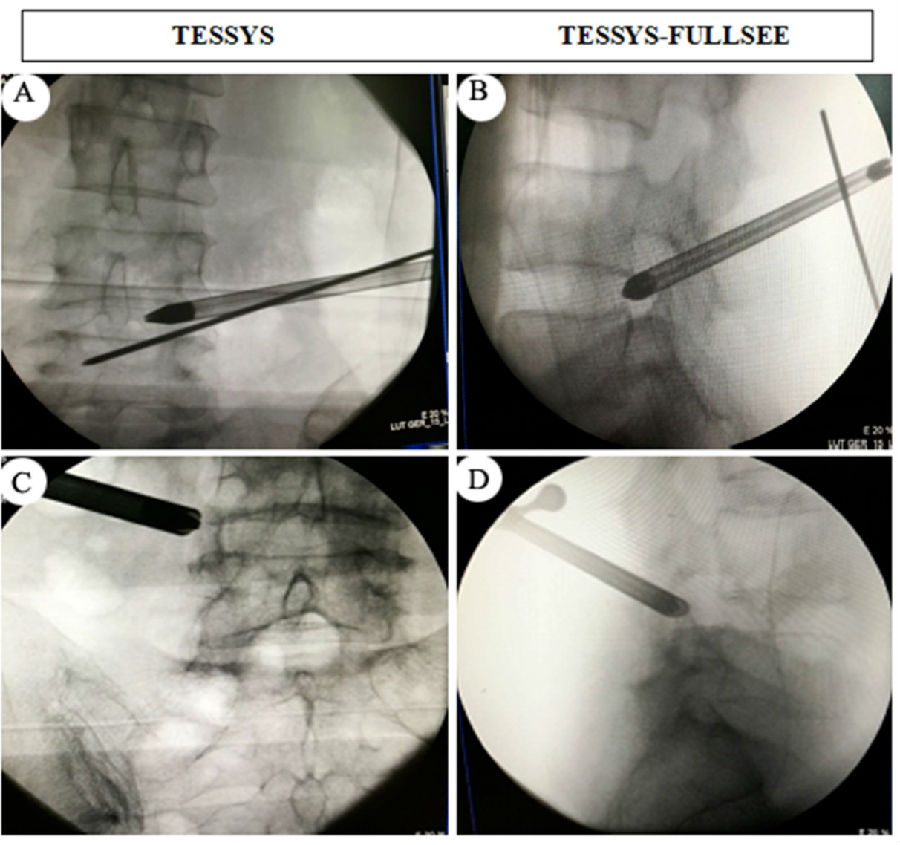

術(shù)中透視.

與傳統(tǒng)的TESSYS技術(shù)穿刺全程需要X線透視相比,我們采用的全麻下的TESSYS-FULLSEE椎間孔鏡技術(shù),術(shù)中常規(guī)只需透視一次,然后在內(nèi)鏡可視化操作下將孔鏡工作套管置入病變區(qū)域。該技術(shù)具有以下特點:1. 真正意義上的全內(nèi)鏡技術(shù),貫穿穿刺至髓核摘除全過程;2.術(shù)中透視少,僅在將通道置入椎間孔后透視正側(cè)位一次,對病人和醫(yī)護人員輻射少;3.整個手術(shù)操作在脊柱內(nèi)鏡監(jiān)視下進行,不易損傷神經(jīng),安全性好;4.采用全麻,病人舒適度高;5.與傳統(tǒng)脊柱內(nèi)鏡技術(shù)相比,精準程度更高,組織創(chuàng)傷更小,減壓更徹底,術(shù)后疼痛緩解更明顯;局麻下手術(shù),患者術(shù)中可能會出現(xiàn)因神經(jīng)根刺激和髓核摘除操作給患者造成難以忍受的劇烈疼痛,術(shù)中需要靜脈輔助強化藥物來麻醉患者;這些弊病,全麻下可以完全避免。